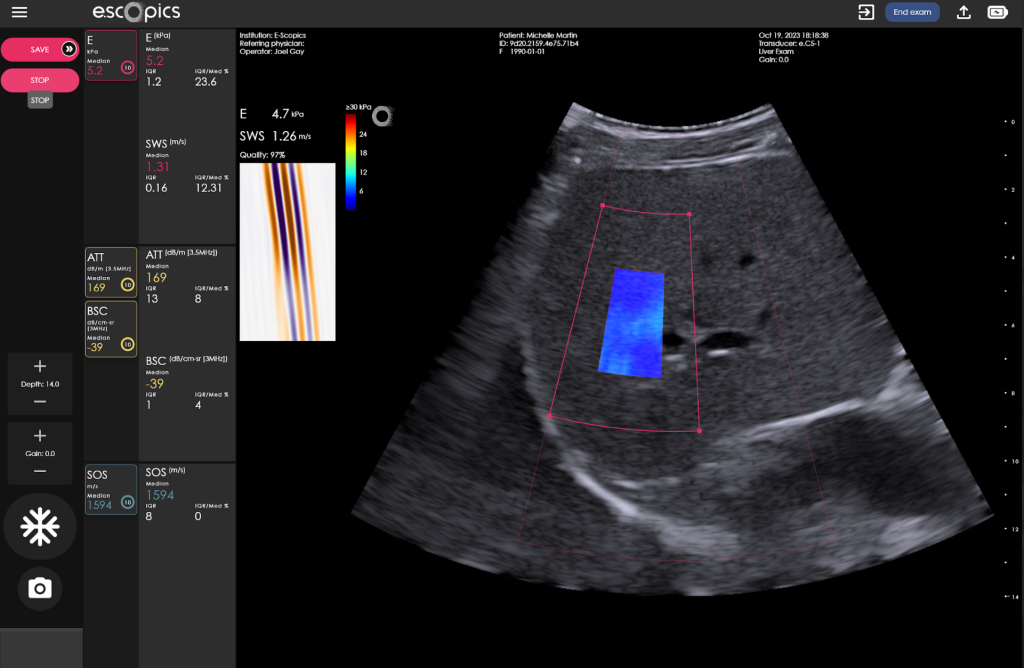

Hepatoscope combines many features to ensure it fits the actual need for early screening of liver disease: ultraportability, 50 Hz transient vibration elastography, ultrafast imaging (real-time stiffness imaging), B-mode image. It has been designed for improved accuracy (repeatability/reproducibility) and applicability.

Leveraging B-mode imaging from conventional ultrasound, Hepatoscope can be used by both novice and expert operators, with good-to-excellent repeatability and reproducibility for liver stiffness and fat quantification.

Its enlarged region of interest is a key feature ensuring a better accuracy of measurements.